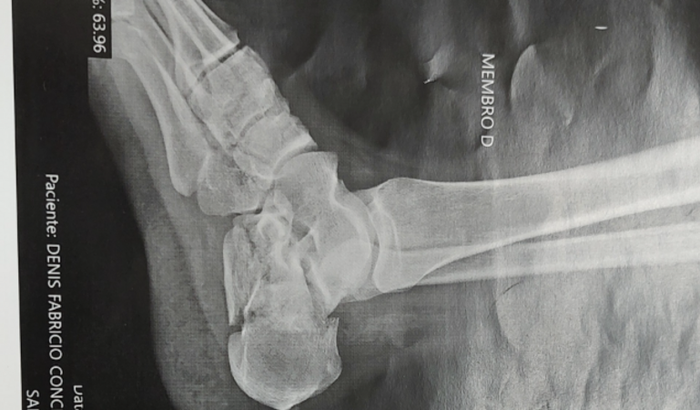

Meu nome é Patrícia. Venho encarecidamente pedir a ajuda de todos neste momento , pois preciso de 15 mil reais pra fazer a cirurgia de calcâneo no meu marido. Ele é trabalhador autônomo, caiu do muro no dia 30/12/22 e fraturou os calcanhares . Cada dia que passa o risco de sequelas é maior , precisa ser feito uma cirurgia urgente . Porém, no hospital publico, além de não ter um médico especialista pra este tipo de cirurgia, não tem vaga . Ele está em uma fila de espera sem data pra operar . Tentei de várias formas arrumar o dinheiro sem ter que optar pela vaquinha ,mas não estou conseguindo. Ele já está fazendo alguns exames necessários. Eu sou trabalhadora autônoma também , porém nesta fase, estou tendo que cuidar do meu marido e tenho um filho especial